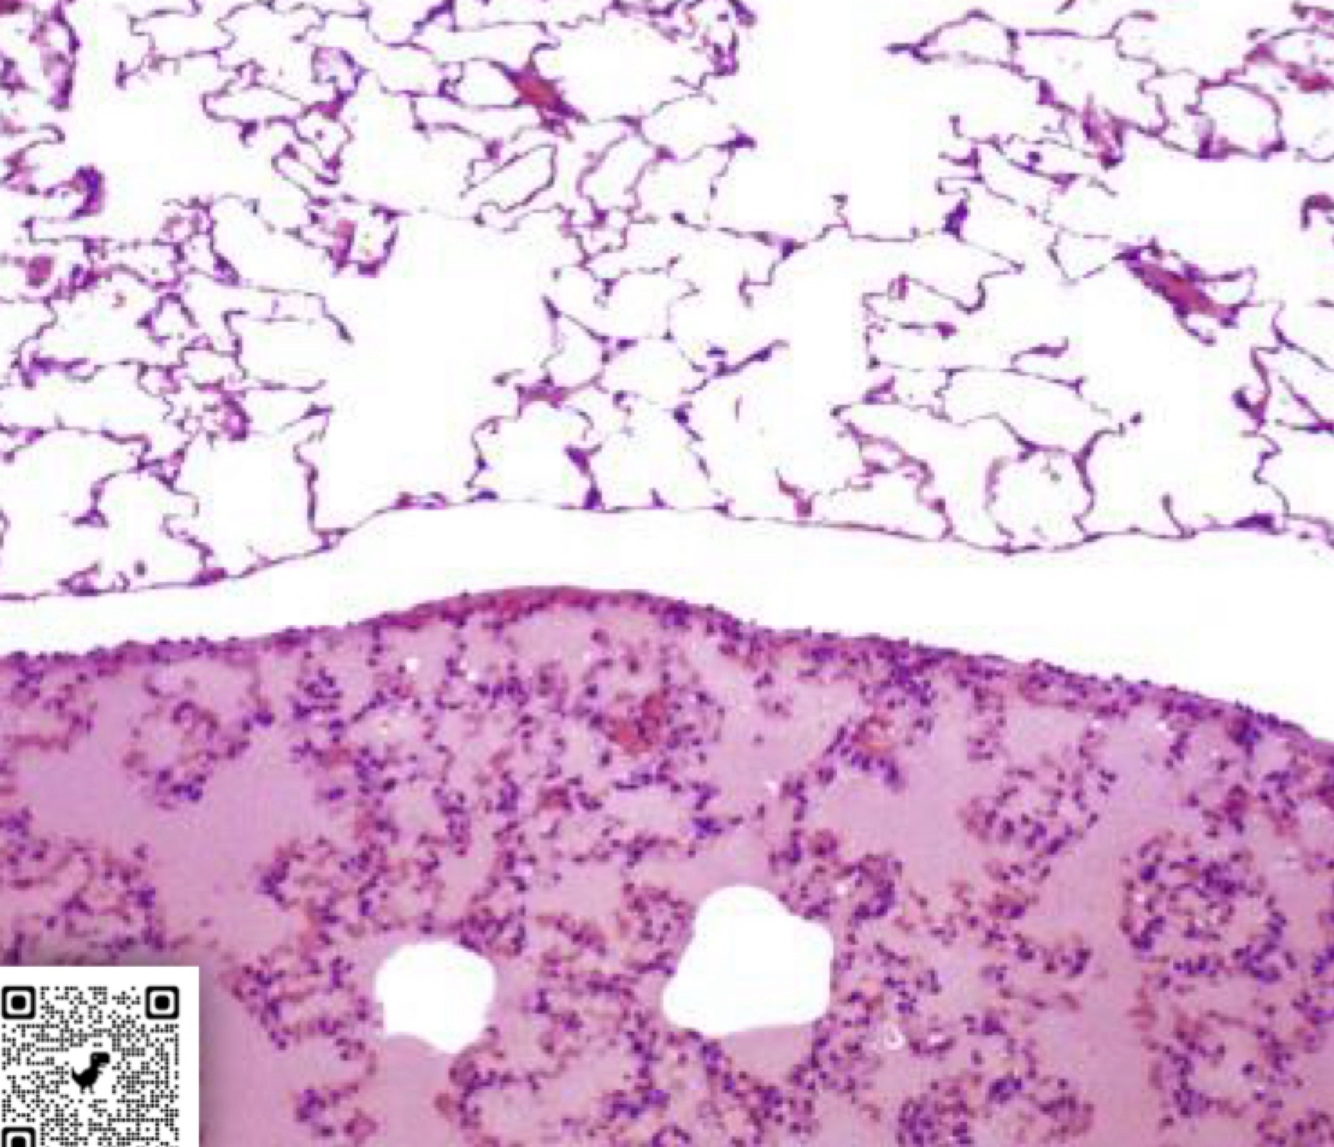

found in = brain (BBB), muscle, lung, bone

Discontinuous Endothelium

A

free transfer of mol, cells, water, etc.

relatively open juncitonal complexes between endothelial cells

also associated with discontinuous basement membrane

seen in = liver sinusoids, spleen sinusoids, bone marrow, lymph nodes